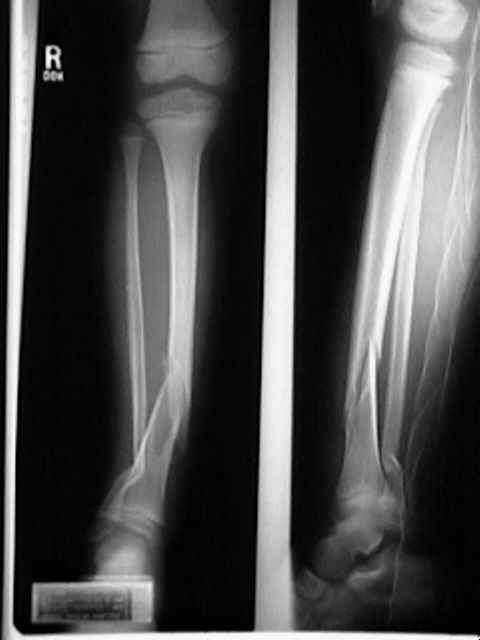

Q.8. What's the Xray finding?

Correct Answer : C